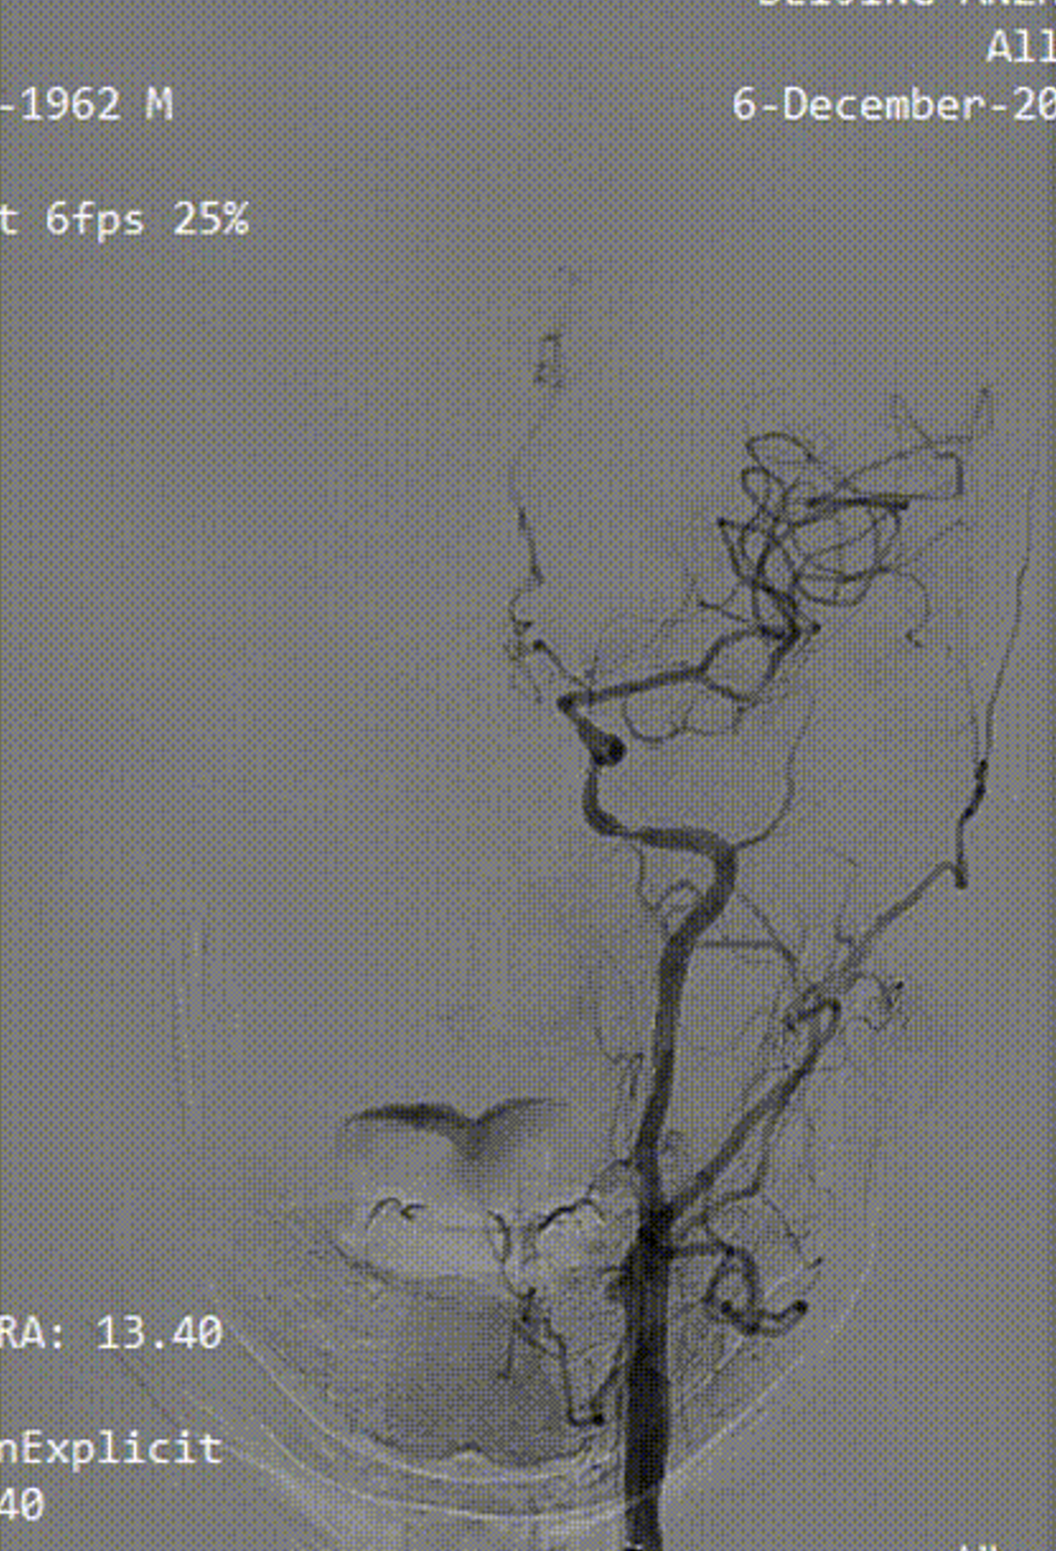

病例2:52岁男性,发作性胸痛2年,体检发现双侧颈动脉狭窄,冠脉情况严重,先行PCI,后行双侧CAS,先右后左,术后复查颈动脉支架通畅。

右侧术前

右侧术后

左侧术前

左侧术后